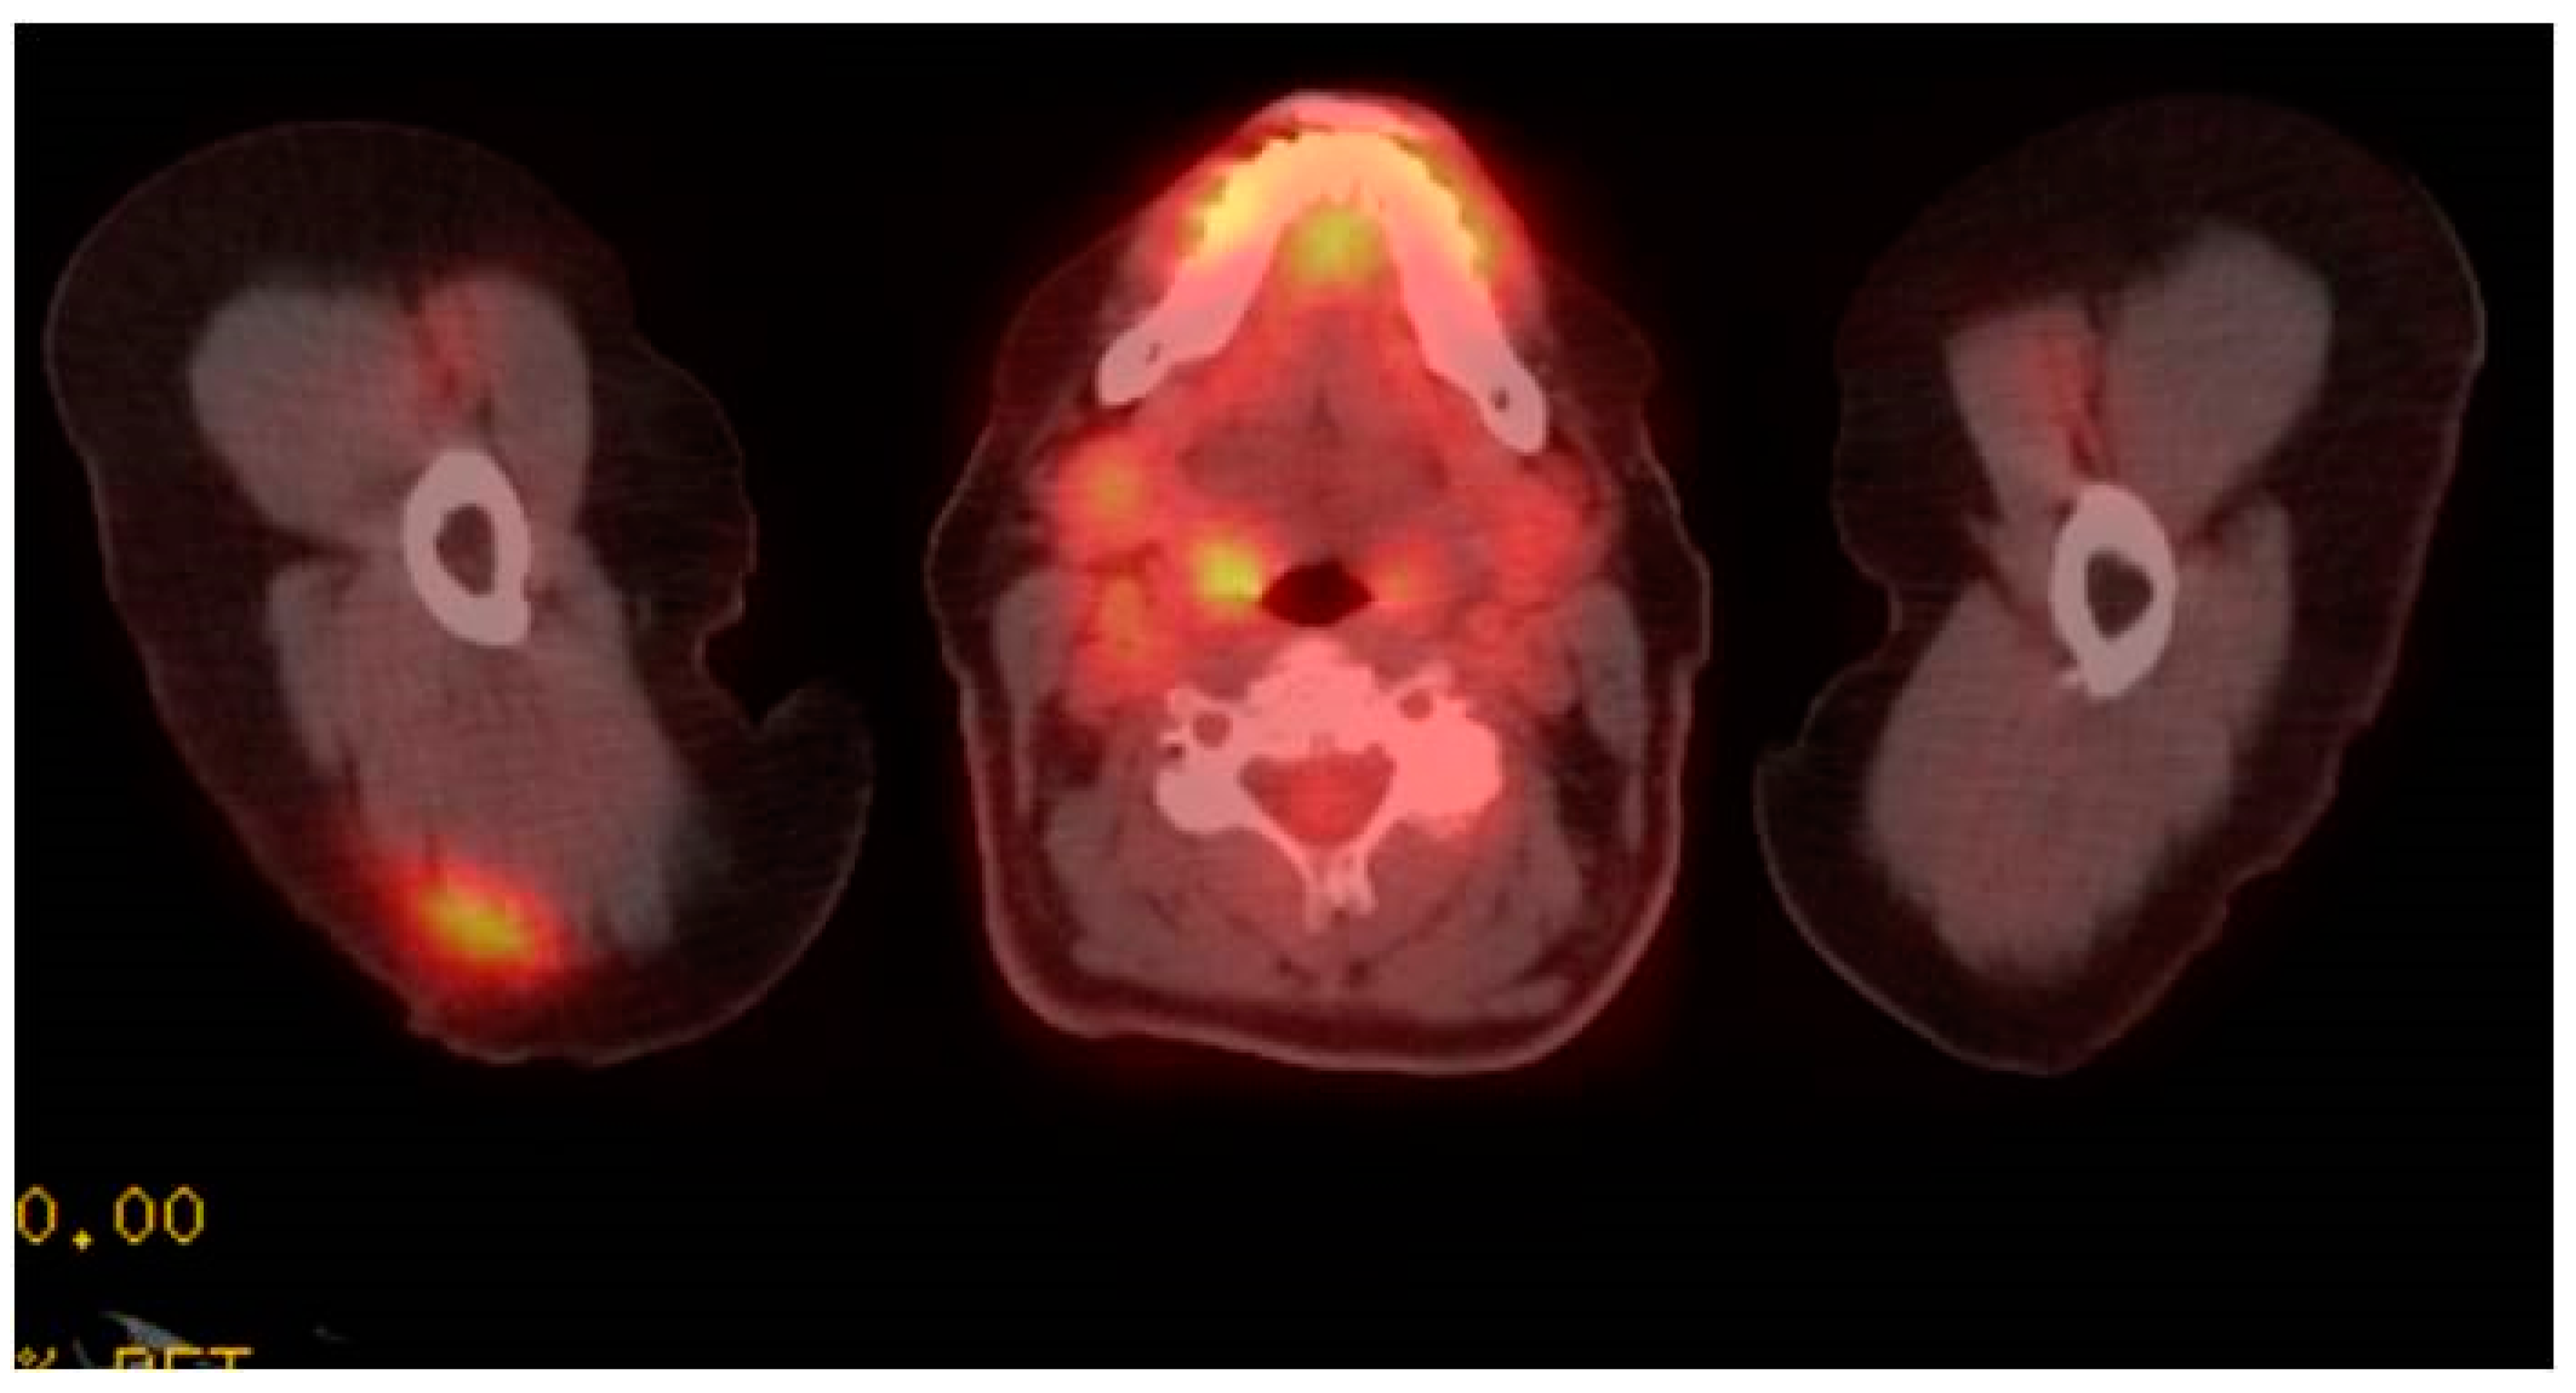

Increased FluoroDeoxyGlucose (FDG) Avidity Following COVID-19 Vaccination